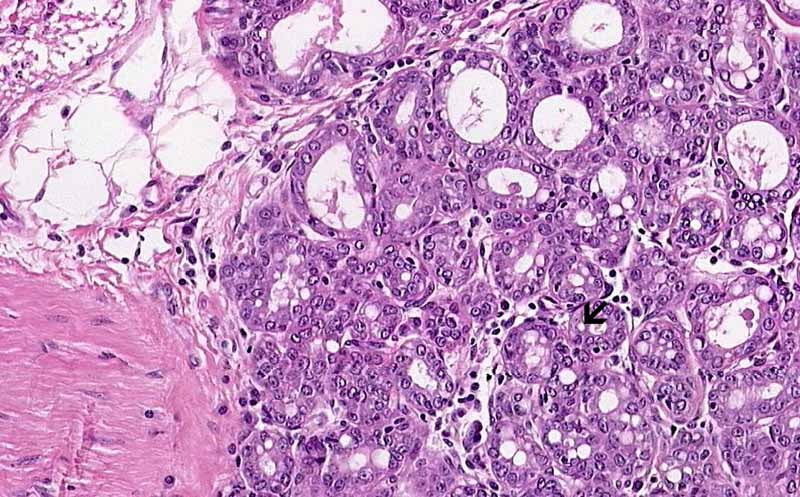

• There is proliferation of glands that arrange in lobules and the overall architecture gives a lobular appearance. In many places, the lobules are separated by adipose tissue (A).

• On higher magnification, the glands have a moderate variation in size and some of them are distended. Vacuoles are seen in the content as well as in the cytoplasm of the cells. These vacuoles represent fat of the milk (Area 1 and 2).

Area 1: Note that the glands are dilated to a variable extent. Intracytoplasmic lipid droplets are present (arrow). The lipid is removed by xylene during processing of tissue and an resulted in an empty vacuoles.